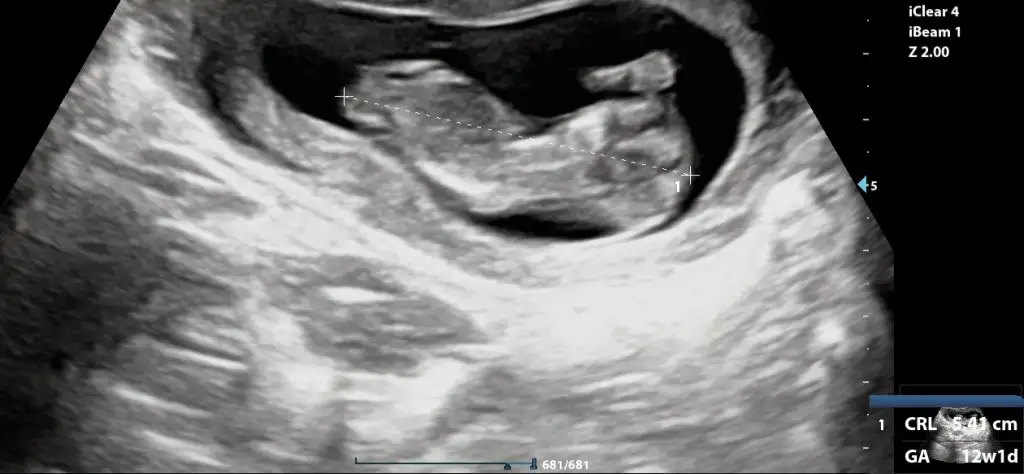

Merhaba erkek gibi benim ultrasonuda yorumlarmisiniz acaba

Eklentiler

• IMG-20240308-WA0003.webp

IMG-20240308-WA0003.webp

12,2 KB · Görüntüleme: 60

Arkadaşlar merhaba daha önce burada ultrason fotoğrafına bakıp cinsiyet tahmin edenleri görmüştüm benim içinde bi heyecan olur:) var mıdır tahmininiz normalde 12+4 üm ama ultrasonda 13 haftalık görünüyor

Erkek gibi hayırlı olsun benim ultrasonda yorumlayacak birisi varımdır acaba